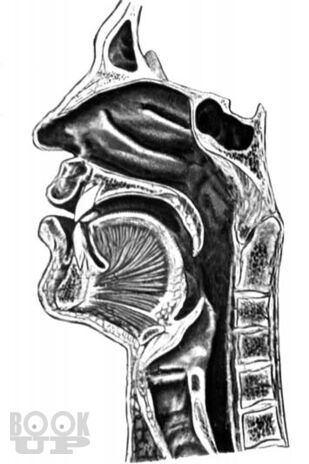

Книга П.В. Власова посвящена традиционным методам рентгенологического исследования пищеварительного тракта. В последние 20 лет периодическая печать заполнена публикациями, посвященными новым, модным и актуальным вопросам применения новейших методов лучевой диагностики, таких как ультрасонография, компьютерная и магнитнорезонансная томография. Между тем как подавляющее большинство рентгенологов в своей практической работе используют традиционные методы рентгенологического исследования, являющиеся базовыми, первичными в клинической диагностике различных заболеваний.